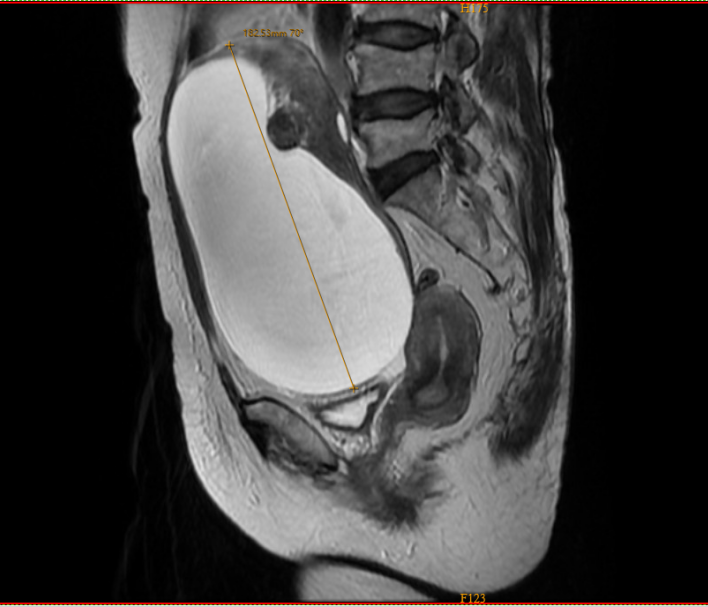

“肚子像揣了大皮球,穿裤紧、摸得硬,觉都睡不好!”71岁的席女士慌了神,当地医院B超显示:盆腹腔长了168x120mm囊实性包块,约篮球大,几乎占满腹部,需尽快手术。

高龄+巨大肿瘤,微创还是开腹?多学科会诊定方案 入院后,我院妇科团队进一步检查确认:包块直径18cm,源于卵巢,良性可能性大,但手术难度高——肿瘤占满盆腹腔,腹腔镜操作空间极小;老人耐受差,开腹并发症风险高,“彻底切除”与“减少伤害”需精准平衡。 恰逢中山大学附属第六医院妇科李锦波教授来院指导,他与我院妇科甄文明主任牵头,联合妇科、麻醉科、影像科、病理科、功能科开展多学科(MDT)会诊,最终敲定:用腹腔镜微创手术,以“控制性穿刺抽吸减压”缩小肿瘤,再精准切除,兼顾安全与微创。 4个小孔“搞定”18cm肿瘤,术后7天顺利出院 手术当天,团队紧密协作。医生仅在席女士腹部打4个0.5-1.0cm小孔,伸入腹腔镜器械:先小心穿刺抽减压防肿瘤破裂,再借高清视野探查脏器关系,确保无粘连残留后,完成全子宫及双侧附件切除术。术中病理证实为浆液性囊腺瘤伴良性性索间质肿瘤,无需扩大手术。 “本来以为要遭大罪,没想到恢复这么快!”术后6小时,席女士能自主翻身进食;术后第1天可在病房散步;术后第7天,指标正常顺利出院。 科普小贴士: 卵巢肿瘤早发现,别等“变大”才就医 妇科专家警示:卵巢巨瘤易破裂扭转引发剧痛,长期压迫还会致脏器缺血坏死。出现腹部莫名隆起、摸到无痛包块且增大、月经紊乱或腹痛尿频,需及时就医。中老年女性建议每年做妇科超声,早诊早治。